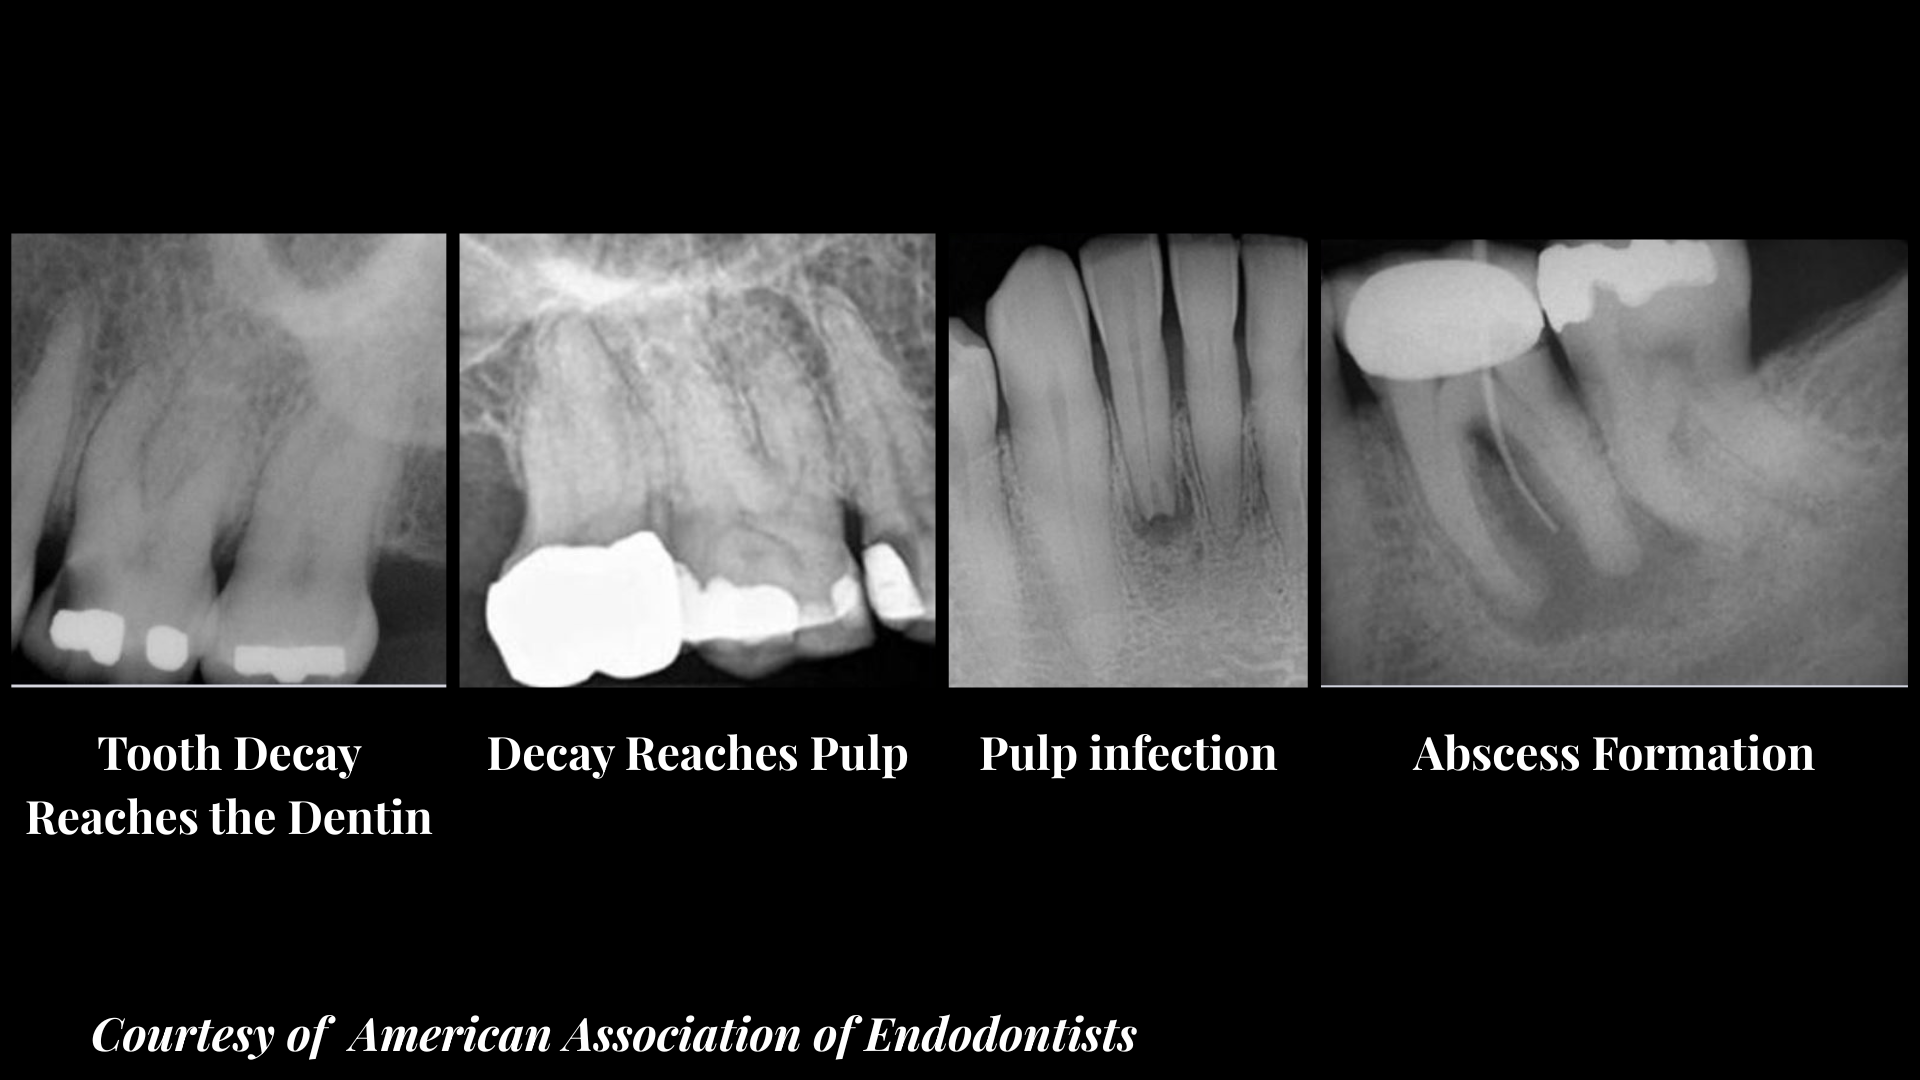

Stage 2: Decay Reaches the Dentin

What You See on X-ray: Larger shadow moving toward the centre of the tooth.

What You Feel: Sensitivity to hot, cold, or sweet foods.

Treatment at This Stage: Deeper filling or possible root canal if the pulp is inflamed.

Stage 3: Infection in the Pulp

What You See on X-ray: Decay clearly into the pulp chamber.

What You Feel: Throbbing toothache, pain at night, swelling of gums.

Treatment at This Stage: Root canal to remove infected tissue and save the tooth.

Stage 4: Abscess Formation

What You See on X-ray: Dark area at the root tip (sign of bone loss from infection).

What You Feel: Severe pain, swelling, possible fever.

Treatment at This Stage: Urgent root canal or extraction if the tooth cannot be saved.